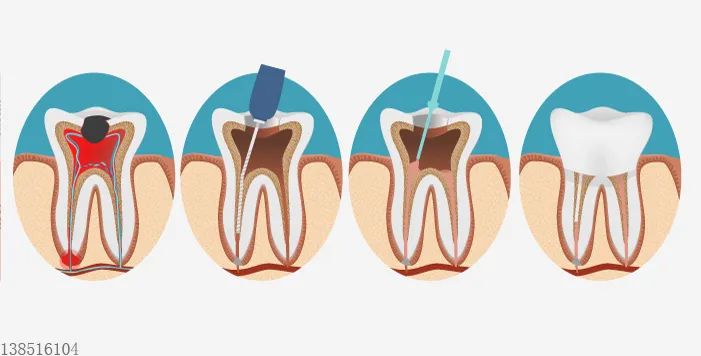

根管治疗的流程是怎么的?

通常情况下

根管治疗需要就诊2~4次

耗时2~3周左右

根管治疗的步骤?

01 钻开腐败的牙质

02 用根管清理牙髓

03 银针锉去牙髓,清洗

04 用专门的材料填充根管

05 用根管钻夸大根管

06 植根 封牙 夯实

07 蓝光照射固化

08 约两周 封牙取膜

最后装上专属牙冠

结束治疗